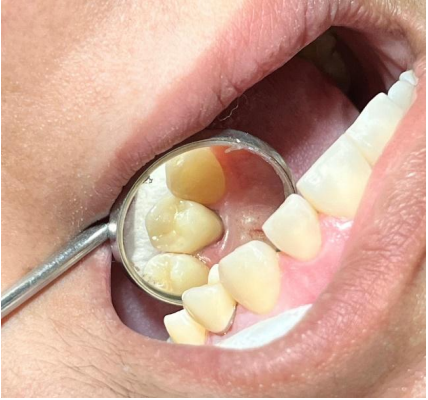

3ª Sessão: Inicialmente foram feitas as limpeza e o tratamento de superfície da coroa com ácido fluorídrico e aplicação de silano. O preparo foi condicionado com o sistema adesivo compatível com o cimento escolhido, após o cimento resinoso ser aplicado na coroa, foi aplicada sobre o preparo sendo assentada cuidadosamente sob leve pressão, o excesso foi removido e a fotoativação do cimento foi feita em toda a periferia, a oclusão foi novamente conferida, sem a necessidade de novos ajustes. Ao final, a paciente apresentou excelente adaptação, estética, e conforto oclusal, em seguida, foram oferecidas orientações de higienização e cuidados, como manutenção e acompanhamento periódico.

Figura – Coroa definitiva em zircônia monotítica

Figura – Coroa definitiva cimentada